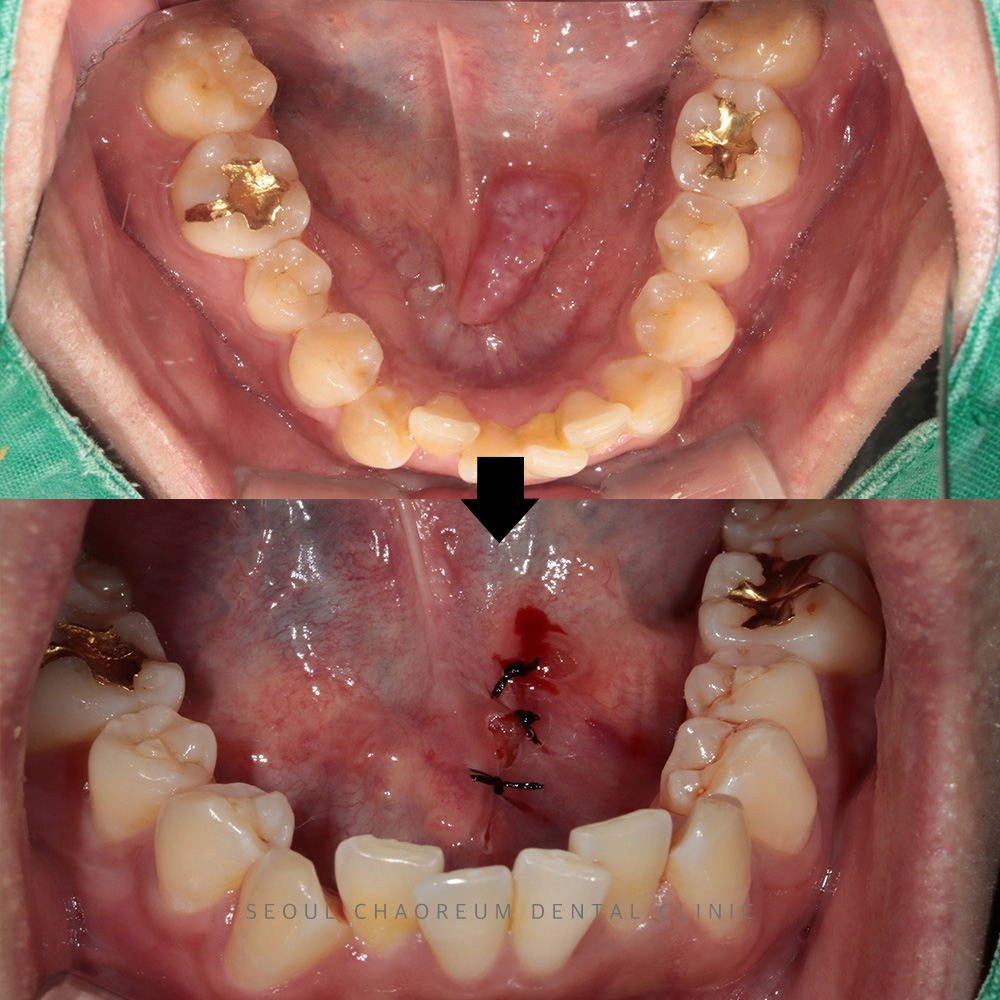

병점치과 혀 밑에 물집 같은 게 생겼어요 혀 밑은 여러 침샘이 모여 있는 부위로, 이 부위에 생긴 이상은 구강 건강에 큰 영향을 미칠 수 있습니다. 특히 하마종은 소타액선의…